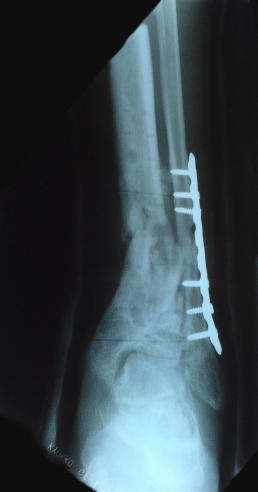

Post-corrective surgery X-Rays of the damaged right & left legs / ankles

The first two x-rays show Liam’s left ankle and pelvis prior to the accident. For comparison purposes it is interesting to see the

differences. The next x-rays were taken after the corrective surgery performed by Dr. Armendariz. Noticed that Dr. Armendariz has used tibia

bracing and also aligned the bone fragments of the left leg so that they could heal in the proper orientation. The external fixation has been

removed and Liam’s left foot has been returned to a more natural alignment.